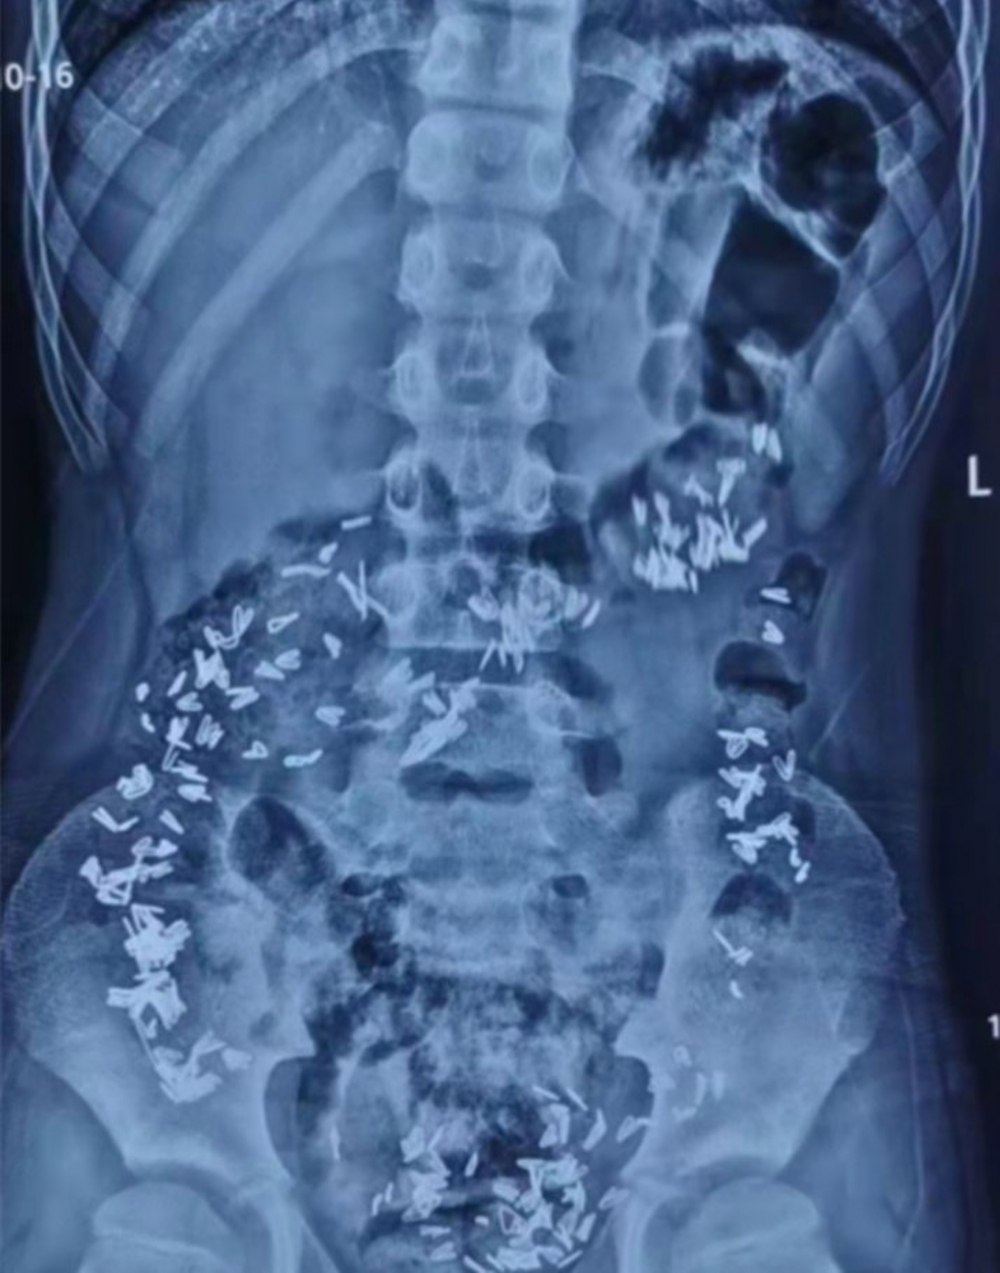

醫生在為男童做X光檢查後,結果讓醫生嚇了一跳。皆因從X光片可見,男童的肚子和腸道全是釘書釘情況嚴重,因此立即安排男童轉到大醫院。轉院後醫院立即組織了消化內科、胃腸外科等醫生進行會診。他們發現男童腹中書釘的數目上百,而且不少已到達小腸,錯過使用胃鏡或腸鏡取出的時機。